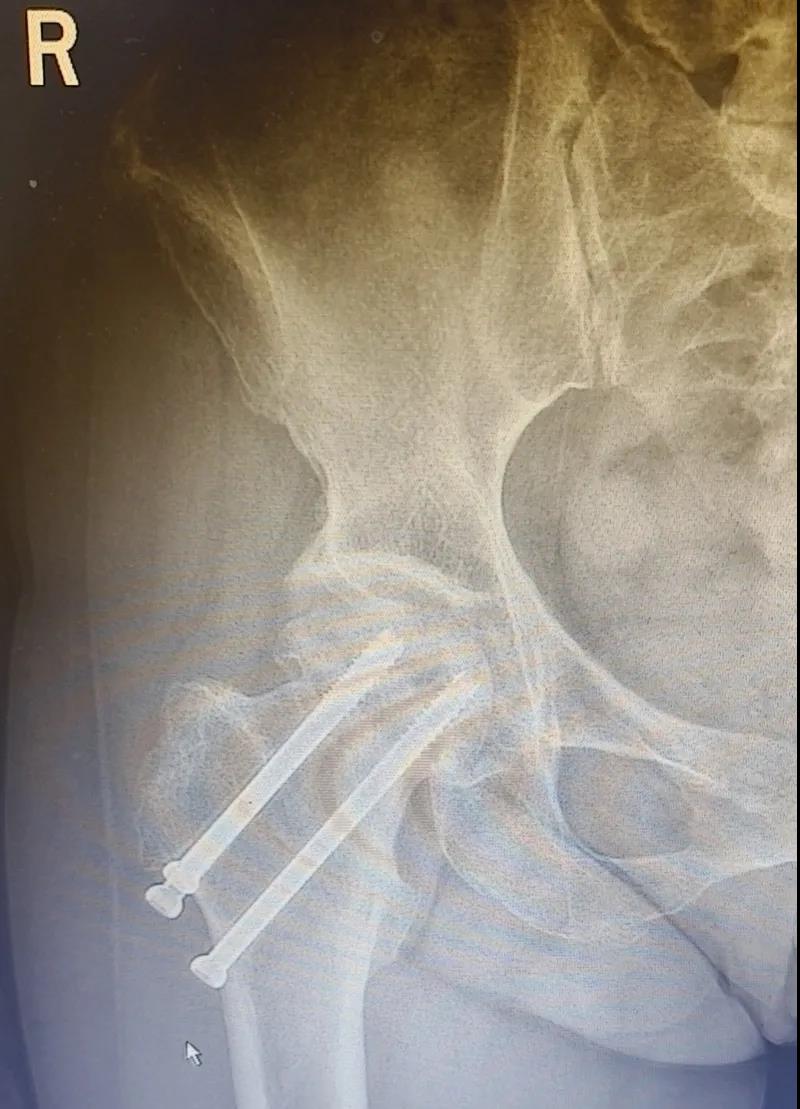

據(jù)李女士自述,自己于3年前因外傷致右股骨頸骨折,當(dāng)時(shí)在其他醫(yī)院做了右股骨頸骨折閉合復(fù)位螺釘內(nèi)固定術(shù),一年后右髖出現(xiàn)疼痛并逐漸加重,且休息不能緩解,行走時(shí)就像有座山壓身上一樣。

結(jié)合病癥表現(xiàn)及影像顯示,李女士被診斷為“右股骨頸骨折術(shù)后股骨頭壞死”,需要盡快做手術(shù)。

(△術(shù)前影像,右股骨頸骨折內(nèi)固定術(shù)后股骨頭壞死)